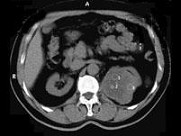

- 多项选择题男性,65岁。左侧腰背部胀痛伴无痛性全程血尿3个月余, CT平扫及增强检查如图所示,下列说法正确的是

A、平扫时见左肾上极有一软组织肿块影,其边界较清楚

B、增强扫描肾皮质期可见肿块明显强化,其内亦有无强化区

C、增强扫描肾实质期可见肿块强化迅速下降,但密度比平扫时仍要高

D、考虑为左侧肾癌

E、考虑为左侧肾错构瘤